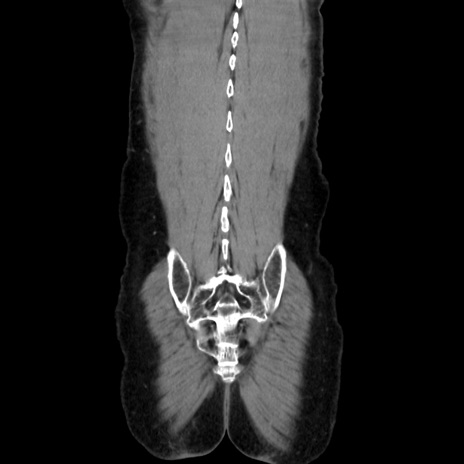

症例37(冠状断像)

【症例】40歳代 男性

【主訴】腹痛

【現病歴】4時間ほど前に電車に乗車中に臍部上より腹痛出現。徐々に増悪し起立困難となり、救急外来受診。生ものは数日食べていない。今朝お雑煮を食べた。

【身体所見】BT 36.8℃、BP 117/84mmHg、HR 91/min、SpO2 97%、苦悶様、腹部:臍上部広範囲圧痛あり、反跳痛±

【データ】WBC 8100、CRP 0.03